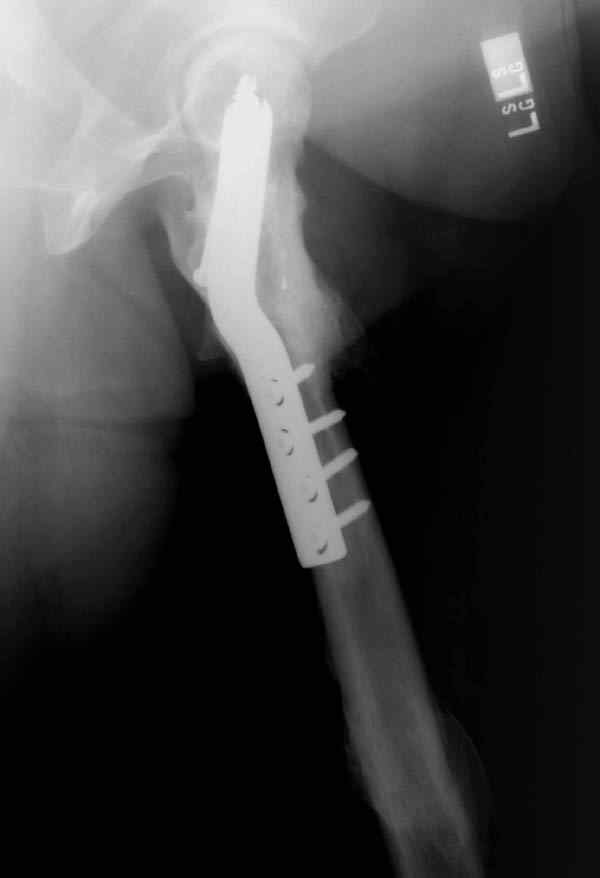

Несмотря на пессимистические прогнозы, у молодых

коррегирующая вальгусная остеотомия является более

приемлемым.

Представленные случаи доказательства тому, что еще

имеется резервы на восстановление даже у 5-6 месячных ложных суставов шейки.